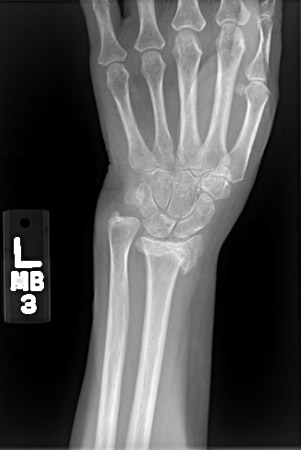

Posteroanterior radiograph showing malunion of the distal radius with significant shortening of the radius and relative lengthening of the ulna

From the collection of Dr Chaitanya S. Mudgal